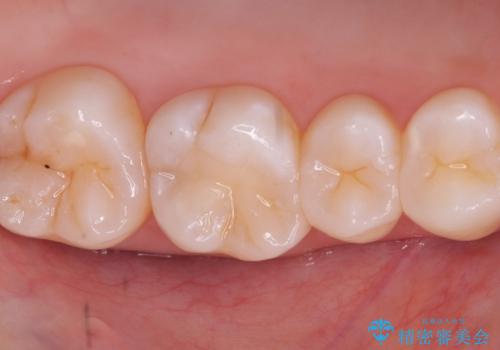

- 主訴:奥歯の噛む面が虫歯になっている。プラスチックの材料で治療可能と言われたが、劣化してまた虫歯になるのが怖いのでセラミックの詰め物にしたい。

咬合面にう蝕があり、CR修復・各種インレーの特徴を説明し、審美性・適合性の良いセラミックインレーでのやり替えとなりました。

咬合面のみのう蝕の場合CR(コンポジットレジン)修復を行うことが多いですが、CRは経年劣化しやすく二次う蝕の可能性を帯びています。それに比べセラミックは着色や収縮が少なく、経年劣化しにくい材料のため、今回はセラミックインレーでの治療となりました。